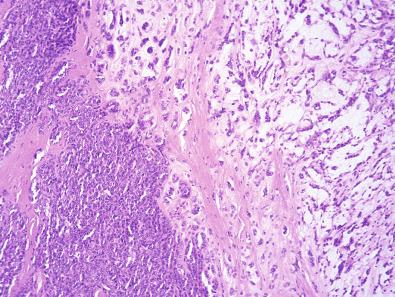

Histologically, conventional MPNST is a spindle cell neoplasm with a fascicular growth pattern, characteristically with alternating hypocellular and hypercellular areas ( Fig. 9.10 ). Tumor cells tend to aggregate around blood vessels. The presence of necrosis and mitotic activity is highly variable; a recent study has suggested that histologic grading of MPNST predicts metastasis and survival. In a subset of cases (depending in part on the extent of sampling), a neurofibromatous precursor can be identified.

Figure 9.10, Malignant Peripheral Nerve Sheath Tumor.

Glandular MPNST is characterized by the presence of scattered glands arranged singly or in small clusters within the spindle cell neoplasm (see Fig. 9.10 ). The glands are usually well defined, appear to be of low grade, and are lined by cuboidal to columnar cells, often with an intestinal-like appearance ( Figs. 9.11 and 9.12 ), sometimes including goblet cells and neuroendocrine cells. Squamous metaplasia, clear cell change, and stromal mucin pools are rare findings.

More common in patients with NF1, MPNST with other forms of heterologous differentiation account for approximately 20% of cases. These tumors are characterized by the presence of malignant mesenchymal elements, most often rhabdomyosarcoma (malignant Triton tumor; Figs. 9.13 and 9.14A ), chondrosarcoma, and osteosarcoma,and more rarely angiosarcoma. The rhabdomyosarcomatous component is usually composed of relatively well-differentiated rhabdomyoblasts with brightly eosinophilic cytoplasm. The presence of heterologous elements is variable in extent, although these elements are usually only focal.

Figure 9.13, Malignant Peripheral Nerve Sheath Tumor With Heterologous Rhabdomyoblastic Differentiation.

Figure 9.14, Malignant Peripheral Nerve Sheath Tumor With Heterologous Rhabdomyoblastic Differentiation.